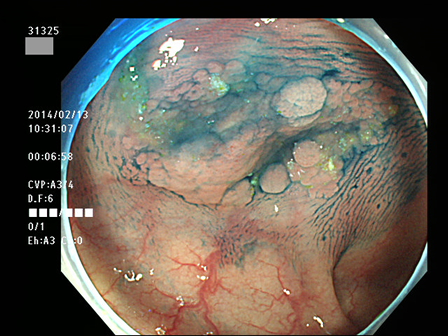

上記100名より抽出した平坦・陥凹型腺腫(=癌化の危険が高いが見落としやすい病変)の内視鏡写真

31320 31321 31322 31323 31324 31325 31326 31327 31328 31329 31331 31332